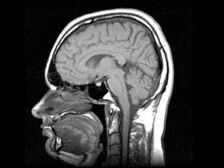

Foto z otevřených zdrojů

Vědci Novosibirsku vyvinuli lék, který vyrábí lidský mozek produkovat kmenové buňky nezbytné pro zotavení nemocných orgánů. “Droga se týká.” regenerativní a nemá na světě žádné analogy. Začínáme tento rok klinické studie, preklinické studie, které jsme dokončili, “- řekl předseda představenstva a spolumajitel společnosti, kdo vyvinul lék, Andrei Artamonov. Podle něj droga způsobuje, že dospělý mozek produkuje nový kmenové buňky, které později najdou poškozený orgán a obnovit to. „U dětí mozek aktivně vytváří kmen buňky, protože dítě roste. A mozek dospělého schopen je produkovat, jen to nechce dělat – pro něj není třeba. Náš lék stimuluje produkci vlastního kmene buňky, “vysvětlil Artamonov. Podle něj všechny operace s kmenové buňky jsou nyní produkovány mimo lidské tělo, které s tím souvisí určité riziko může se zahájit modifikovaná, uměle pěstovaná buňka komunikovat na neočekávaném místě. Buňky lze zadat, ale to vždy riziko, protože není úplně jasné, kde jsou rozlišit. I když jsou vaše, jsou propagovány mimo vaši organismus. Vlastní kmenové buňky tam nemohou selhat rozlišit. Najdou poškozený orgán a začnou to obnovit tělo, “dodal Artamonov. Klinické zkoušky droga vydrží rok a půl, hlásí Interfax.